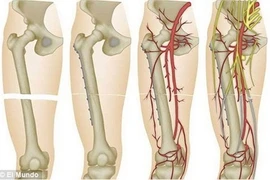

Nút mạch lấy u máu khổng lồ trong xương chậu cho trẻ 12 tuổi

(khoahocdoisong.vn) - Chỉ nghĩ con bị đau xương tuổi dậy thì nào ngờ trẻ 12 tuổi bị  u máu khổng lồ phá hủy nửa cánh xương chậu và đe dọa tính mạng. Nhờ kỹ thuật nút mạch và ghép xương, các bác sĩ tại hai bệnh viện kết hợp đã loại bỏ thành công khối u máu và trám xương thành công cho trẻ.